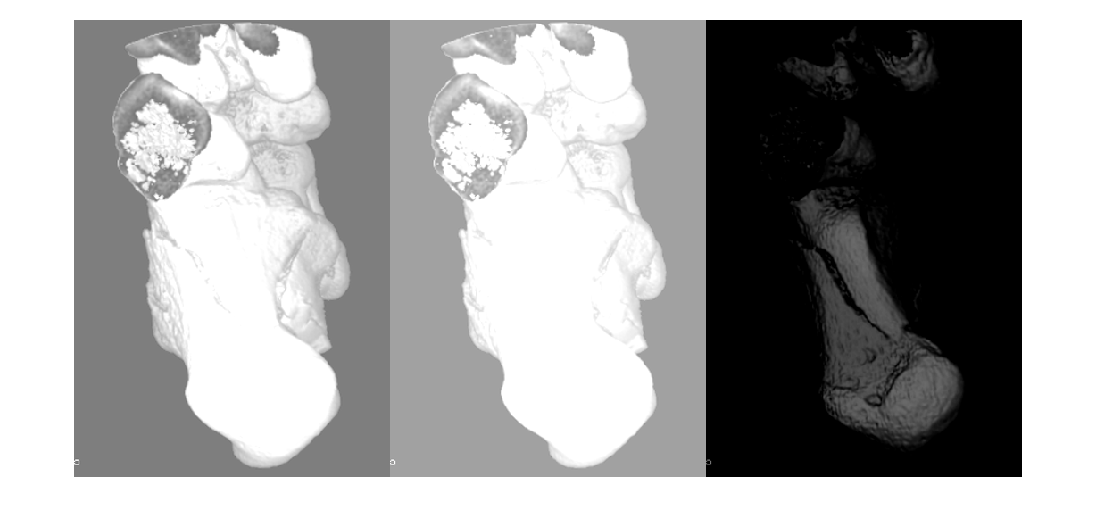

augmentation, or color augmentation. The jitterIntensity function performs

intensity augmentation of grayscale images and intensity volumes by randomly augmenting their

brightness, contrast, and gamma correction.